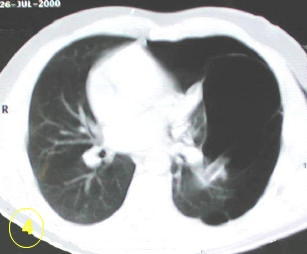

La tomografía computarizada del tórax

y su adecuada interpretación es de gran ayuda diagnóstica

en las patologias del tórax.